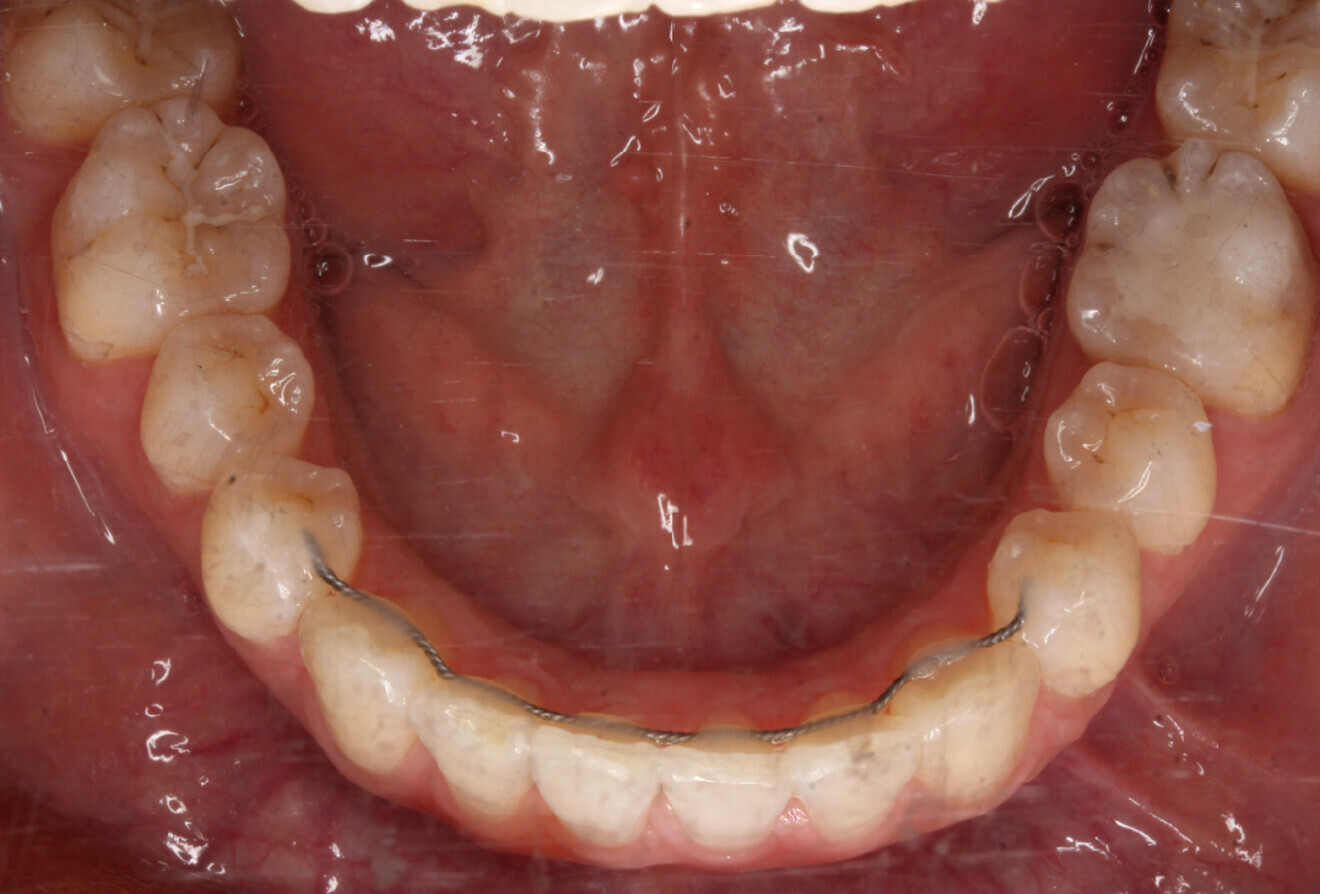

Fig. 4d: Occlusal intra-oral view of the mandible.